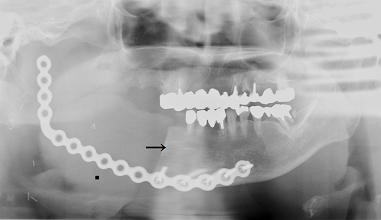

下顎骨区域切除後のXP (水川 他:岡山医誌 ,2008)